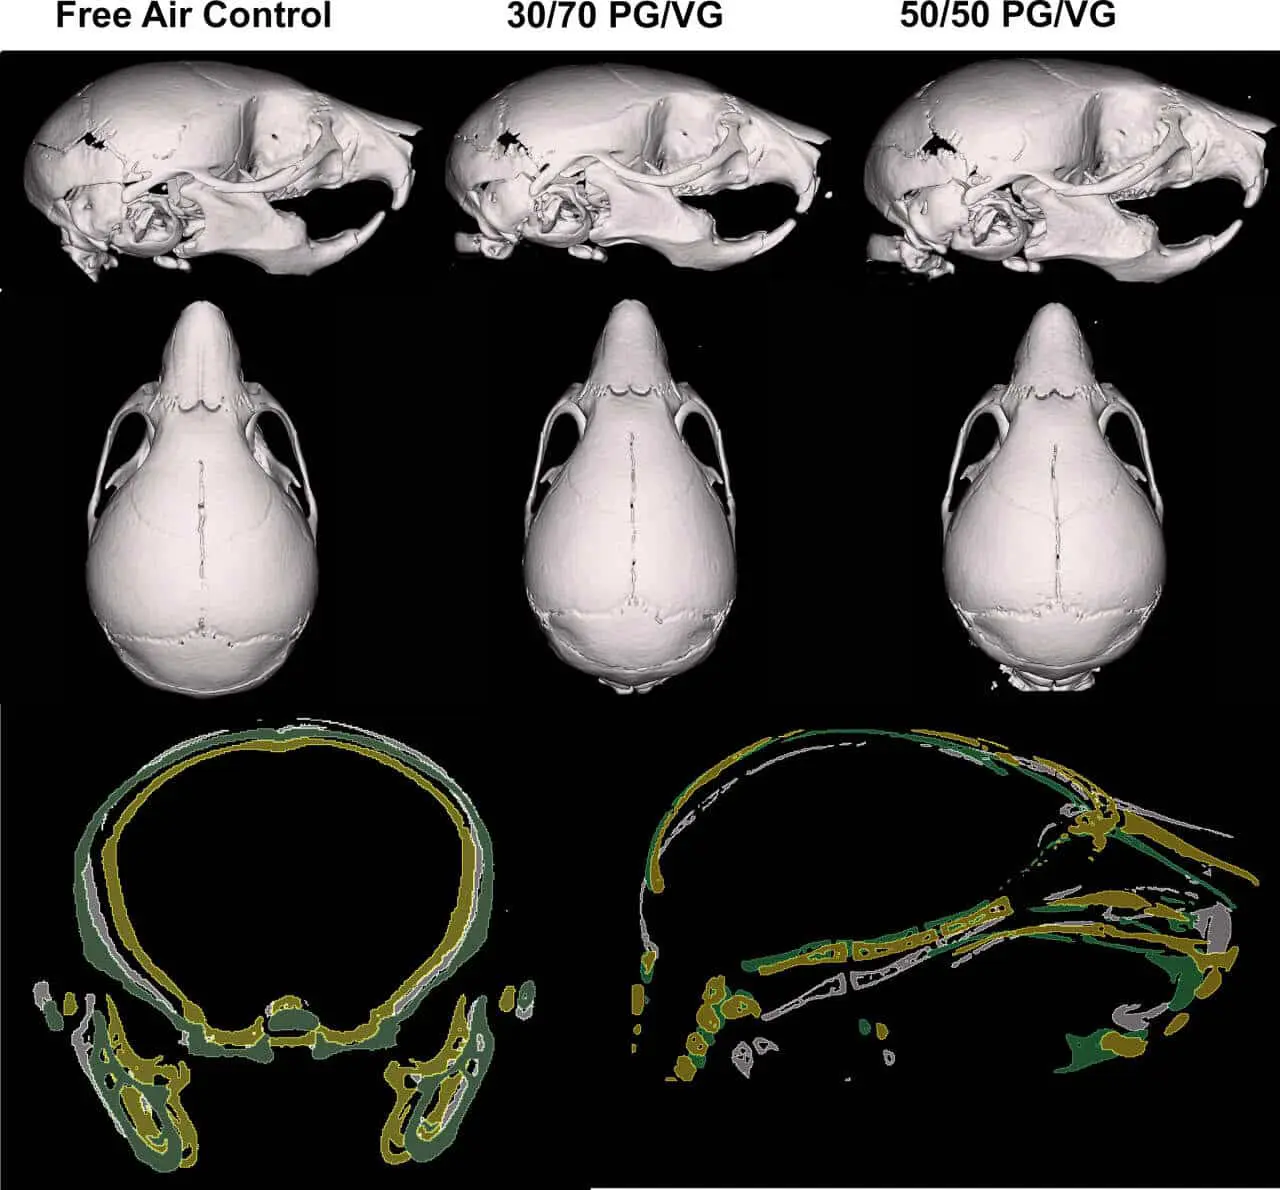

В ходе новой экспериментальной серии ученые решили выяснить, как скажется на состоянии потомства влияние безникотиновых смесей в вейпах с разным содержанием пропиленгликоля и глицерина (PG/VG 30/70 и PG/VG 50/50). Для этого были выбраны две группы самок лабораторных мышей известной линии C57BL6. На протяжении всего периода беременности животных ежедневно помещали в условиях, где они вдыхали аэрозоль электронных жидкостей той или иной рецептуры по четыре часа, пять дней в неделю. Контрольная группа вдыхала исключительно фильтрованный воздух.

После появления на свет, каждое новое поколение мышат находилось с матерями две недели, что дало ученым время наблюдать за их развитием. На четырнадцатый день малышей подвергали эвтаназии для проведения объективных замеров. Были тщательно проанализированы масса тела и форма черепа с использованием микрокомпьютерной томографии — передового с точки зрения точности метода визуализации костных структур.

Результаты экспериментов оказались впечатляющими. Мышата, матери которых вдыхали смесь с низким содержанием пропиленгликоля (30%) и высоким содержанием глицерина, по массе уступали сверстникам, отличались более короткими черепами и суженными мордами. При сравнении групп, в которых использовались разные рецептуры смесей, оказалось, что выраженные отличия касались именно группы с пониженным PG. А вот потомство самок, подвергавшихся воздействию аэрозоля с равным содержанием PG и VG (50/50), не продемонстрировало отличий от контрольной группы, дышавшей обычным воздухом.